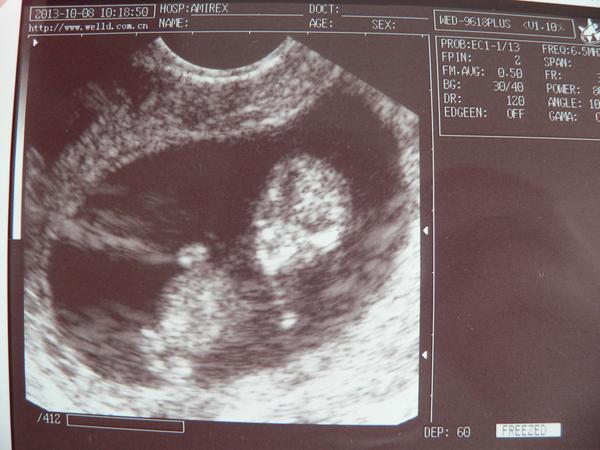

@cital jůů supèr,že je mimísek na svém místě a fotečka je překrásná. Ještě jednou gratulace .takže jsi v kolikatem týdnu? A proč krev nedělají současně? S ultrazvukem? Me to dělali v jeden den a to jsem byla 13+1 myslím tak nějak. No ale hlavní ž jste v pořádku a nasadila ti nějaké léky?

@ofina1 Jsem strašně šťastná 🙂. Jsem dnes 10+2, dle UTZ 11+0. Krev by měla být brána do 11tt (budou mi vyšetřovat navíc srážlivost, kvůli ségry), UTZ by měl být dělán okolo 13tt. Já beru kočko od začátku utrogestan (2 večer) a ještě ho budu asi 2 týdny brát.